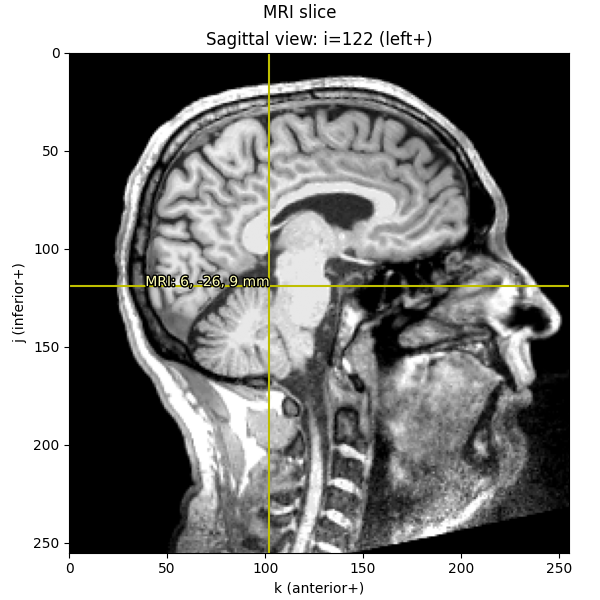

Knowing these relationships and being mindful about transformations, we can get from a point in any given space to any other space. Let’s start out by plotting the Nasion on a sagittal MRI slice:

fiducials = mne.coreg.get_mni_fiducials(subject, subjects_dir=subjects_dir)

nasion_mri = [d for d in fiducials if d["ident"] == FIFF.FIFFV_POINT_NASION][0]

print(nasion_mri) # note it's in Freesurfer MRI coords

<DigPoint | Nasion : (2.6, 99.8, 40.8) mm : MRI (surface RAS) frame>

When we print the nasion, it displays as a DigPoint and shows its

coordinates in millimeters, but beware that the underlying data is

actually stored in meters,

so before transforming and plotting we’ll convert to millimeters:

nasion_mri = nasion_mri["r"] * 1000 # meters → millimeters

nasion_vox = np.round(apply_trans(np.linalg.inv(Torig), nasion_mri)).astype(int)

imshow_mri(

data, t1, nasion_vox, dict(MRI=nasion_mri), "Nasion estimated from MRI transform"

)